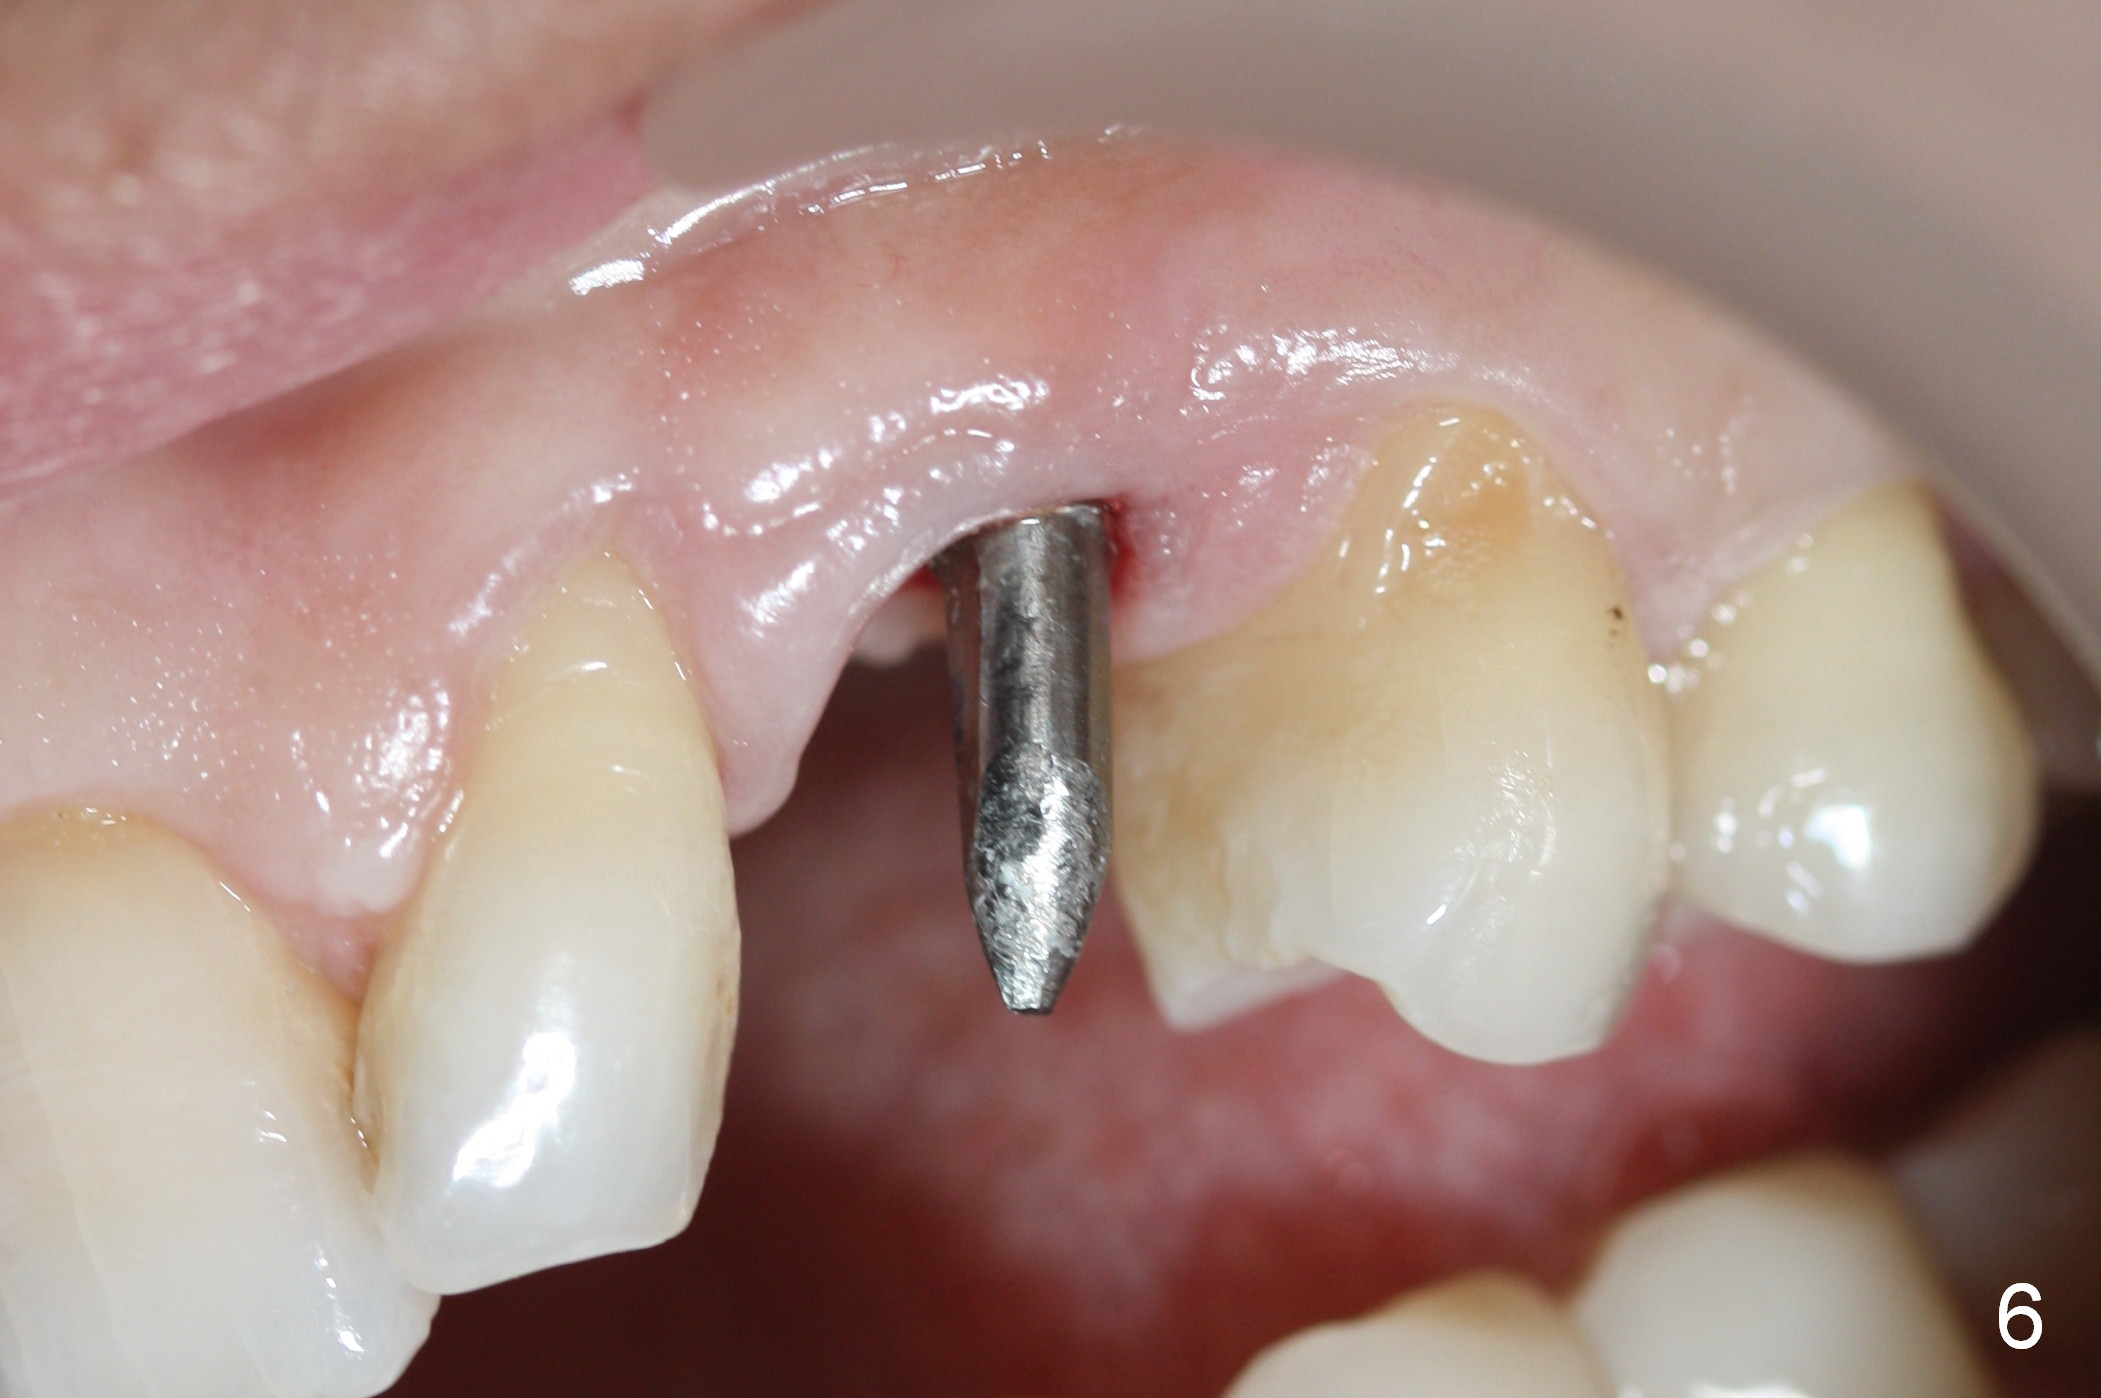

The ridge looks wide clinically 4 months post implant removal and socket preservation. In fact, the graft bone is soft and the ridge is narrow after incision. It appears that an angled 1 piece implant is an indication. A 1.2 mm pilot drill is used to start osteotomy. At approximately 17 mm, the patient feels pain. The nasal floor perforates? A 2 mm osteotome is utilized to enlarge the osteotomy. At 17 mm, the osteotome is stable (Fig.1), but the nasal floor appears out of view. Review of the preop PA shows that the distance between the gingival margin and the nasal floor (arrowheads) is ~22 mm (Fig.2). It should be safe and necessary to place a 3x20 mm 1-piece implant with 15° angulation. Insertion torque is between 40 and 45 Ncm.

Intraop PA shows that the nasal floor is perforated (Fig.3). The patient experiences bilateral nasal obstruction. Sneezing produces trace of hemorrhage from the left nostril and large amount of secretion from both nostrils. The nasal speculum is misplaced in the clinic. Clinical nasal floor perforation cannot be confirmed. After abutment preparation, an immediate provisional is fabricated. Afrin is prescribed. Post-op instruction includes continuing Amoxicillin and Chlorhexidine rinse. A few hours postop, the patient reports no abnormality.

Six days postop, the patient is doing fine without nasal symptoms. Nasal speculum exam does not reveal apparent nasal floor perforation. The perio dressing remains around the provisional (Fig.4,5 P). Local scaling is provided for slightly tender palatal gingiva between the provisional and the neighboring tooth (Fig.5 ^). Continuous Chlorhexidine rinse is recommended.

Eight months postop, the patient returns for #11 restoration. She reports no problem at #11, while there is light tenderness with a 2-piece implant (4.5x20 mm) at #6 at night (Fig.10, a portion of panoramic X-ray). Clinical exam reveals no abnormality at #6. Although the implant at #11 is buccally placed, there is no buccal plate atrophy (Fig.6,7). In fact the 20 mm 1-piece implant is placed in the bone (septum) between the nasal cavity (Fig.10 pink dashed line; Fig.13 (CBCT (52 year-old lady) N) and the maxillary sinus (yellow dashed line, S). In fact the apparent nasal floor indicated as arrowheads in Fig.2 and 10 is the horizontal plate of the palatine bone (hard palate)! Therefore there is no nasal floor perforation in this case. A long implant is indicated in the upper canine.

The main reason for the failure of this case is buccal placement of the implant (Fig.11 A: abutment). Every time an implant is placed at the upper anterior, make sure that palatal placement is done (Fig.12 *). The most critical step is the 1st pilot drill. If the position is not ideal, use a Lindemann bur for adjustment. Check repeatedly. If the implant starts to be deviated buccally, remove the implant, use the Lindemann bur to remove more of the palatal bone and place the implant palatally.